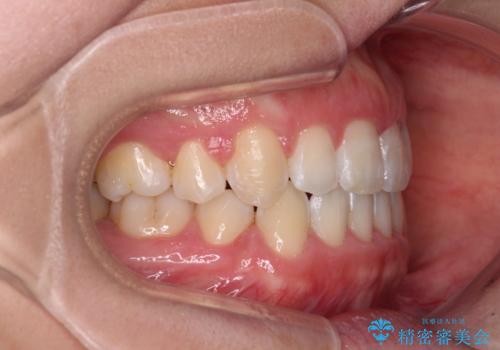

- 口元の突出感と口の閉じにくさ、前歯のデコボコを気にして来院された患者様です。

上下左右第一小臼歯4本を抜歯し、ワイヤー装置にて口元を引っ込めるよう矯正治療を行うこととしました。

骨格的に下顎骨が前方位にあるため、口元の突出感改善には限界があると思われましたが、唇の閉じにくさが改善するほど引っ込めることができました。